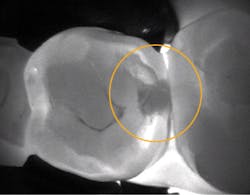

Intraoral image using DEXcam HD

Transillumination image using CariVu

I also have a CariVu (DEXIS) caries detection system, which uses near-infrared transillumination. CariVu does not generate ionizing radiation and produces images that look similar to x-rays. If I see an early lesion on an interproximal surface that I would like to remineralize, I take a secondary CariVu image of the area. CariVu helps me visualize the area of concern from the bucco-lingual and the mesio-distal aspect with a 99% accuracy rating.1

My DEXcam HD (DEXIS) digital camera completed my imaging protocol. I had used different intraoral cameras in the past, and the improvement in image quality was amazing. Today, I use photographs for documentation and patient education. When a patient returns for recall, we have a photo of the tooth and can see if it has changed. Sometimes we take before-and-after pictures if patients have substantial calculus buildup, cracked teeth, or restorations with margins breaking down. We take photos when they have teeth that require treatment, and this motivates them to accept my recommendations and improve their oral care. In the DEXIS software, I have radiographs, caries detection, and digital photographs all at my fingertips.